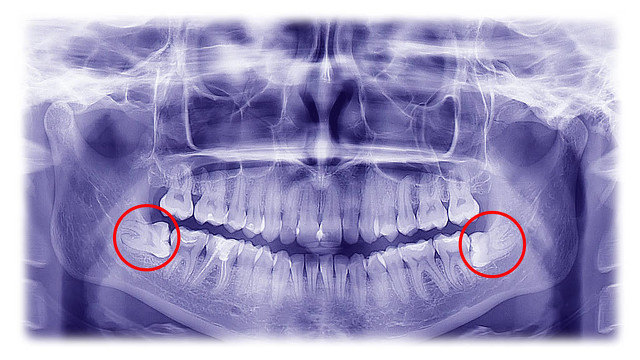

4、智齿冠周炎

智齿处出现牙龈肿胀疼痛,咀嚼吞咽受限或者疼痛,严重的甚至无法张口且伴随发热,脸部肿胀情况。

出现这种疼痛的症状可以使用生理盐水反复漱口和人工牛黄甲硝唑进行消炎止痛。